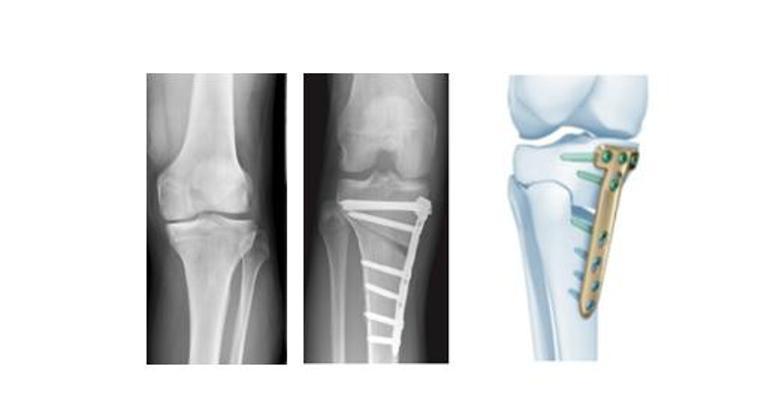

Resim: Dizin iç kısmında kıkırdak hasarı (kireçlenme), bacaktaki eğilme ve yük aktarma ameliyatı

Bu aşamada yani eklem kıkırdağındaki aşınma (kireçlenme) eklemin sadece bir tarafında iken bacaktaki içe eğrilik ameliyatla düzeltilerek (osteotomi) bacağın iç kısmını yükten kurtarıp yükün dış tarafa gelmesi sağlanır. Bu ameliyat bacağın bozulan dizilimini (eğilmesini) düzeltir. Hasarlanan kısımdan yükün daha sağlıklı kısma aktarılmasını sağlar. Hastanın eklemini koruyucu bir ameliyat olan yük aktarma ameliyatı ile iç taraftaki kireçlenmenin ilerlemesi durdurulur veya en azından yavaşlatılır. Dizde kireçlenmenin tedavisinde uygun hastalarda yapıldığında bu ameliyat ile hem hastanın ağrısı geçer hem de protez uygulanmasına gerek duyulmaz veya uygulanma yaşını geciktirir.

Bu ameliyat özellikle protez ameliyatı için daha genç, daha az ciddi eklem hasarı olan ve daha aktif hastalarda tercih edilir. 65 yaşından daha genç, aktif hastalarda ameliyat dışı tüm tedavilerin denenmesine rağmen diz ağrıları geçmiyorsa protez tedavisinden önce yük aktarma ameliyatı uygulanır. Dizdeki kireçlenme eklemin sadece bir tarafındayken etkilidir. Dizin dış tarafı normal olmalıdır. Ameliyat öncesinde bacağın dizilimini görmek için tüm bacağı içine alan boy grafisi çekilir. Boy grafisinde bacak aksının (mekanik aks) iç tarafa kaydığı görülür ve ölçülen dereceye göre yapılacak düzeltme planlanır. Ameliyat sırasında diz eklemini açmadan kapalı yöntemle (artroskopi) eklemdeki menisküs yırtığının tedavisi ve kıkırdak kaybı olan bölgelerde yeniden kıkırdak oluşumunu sağlayıcı (mikrokırık) işlemler yapılır. Daha sonra bacağın üst iç kısmından 7-8 cm’lik cilt kesisinden kemiğe ulaşılarak eğilmenin derecesine göre küçük bir kemik kesisi ile bacaktaki eğilme düzeltilir ve yükün dışa aktarılması sağlanır. Düzeltme yapıldıktan sonra plak ve vidalar ile arzu edilen düzeltme pozisyonunda açılan kemik uçları tespit edilir.